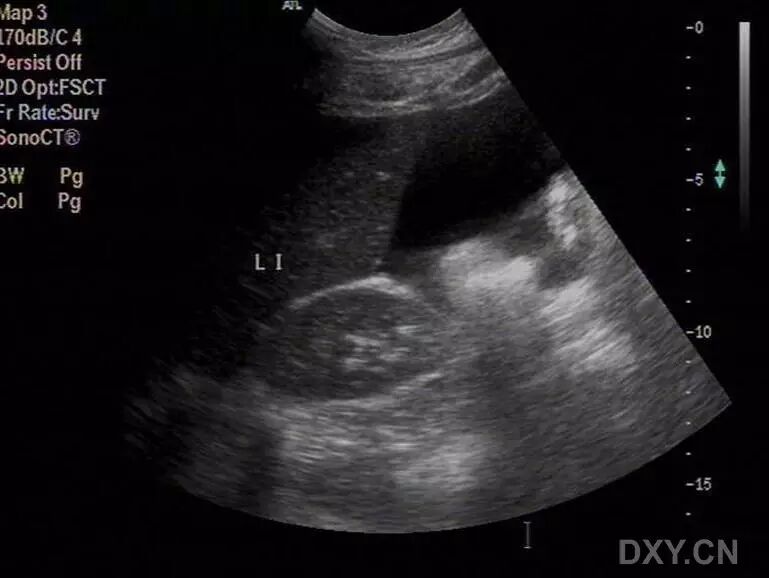

病例1(由丁香园注册用户「微蓝水色」提供):26岁女性,已婚,自觉腹胀不适就诊。

超声检查发现子宫大小正常,双侧附件区多囊性包块,盆腔大量积液,胸腔积液。肝胆胰腺肾脏及膀胱未见明显异常声像。

追问病史,患者多囊卵巢治疗后拟怀孕,最近正服用促排卵药物。

患者治疗后两周复查,盆腹腔积液消失,胸腔少量积液,附件包块明显缩小,能够分辨出卵巢形态。

结合病史,考虑为卵巢过度刺激综合征表现。

以下图片为第一次检查时的图片:

图1 显示子宫周边积液